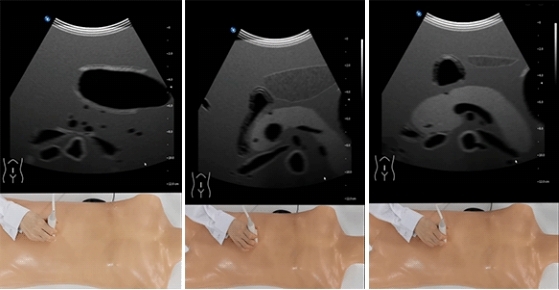

4.6教學功能下,可以在三維圖像和超聲圖像之間切換或同時顯示,學生可以根據(jù)解剖結(jié)構(gòu)更好的理解超聲圖像;

4.7訓練功能下,模擬真實的超聲環(huán)境,用戶根據(jù)所選病例,選擇正確的探頭在模擬人上操作,顯示對應(yīng)模式下的超聲圖像,可隨時調(diào)整參數(shù)和圖像效果,包括B、CF、M、PW、CW模式視圖選擇、增益、縮放、深度等;

4.10切面測評:選擇測試的切面,參照標準切面超聲圖像,找到切面后自動測評。界面包括標準切面的超聲聲像圖,用戶實時操作的三維圖像和超聲聲像圖??蓪W生選擇的超聲切面進行自動評定;